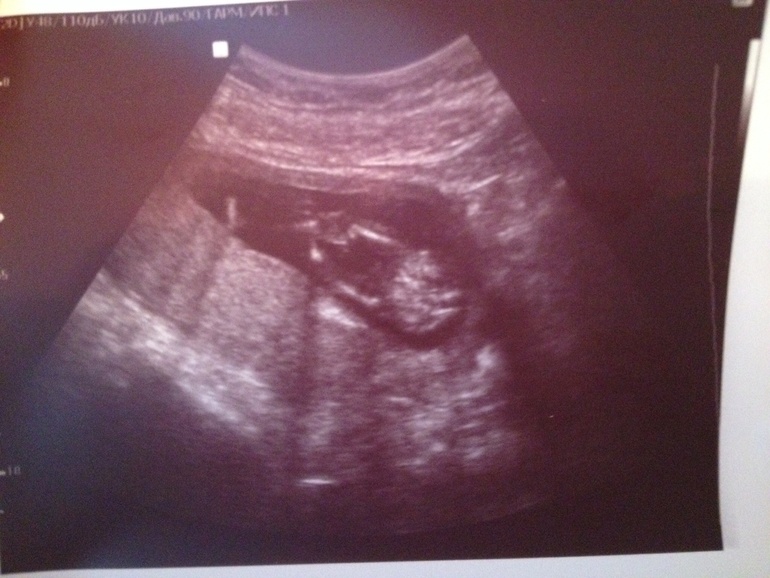

Алина 11 лет Доченька!!! Растем здоровые и длинные) Врач говорит, что родиться будущая модель) Мы очень ждем тебя, Маруся! Посмотрите еще 20 записей на эту тему Отменить Ответить Узи! Первые шевеления! Чаты Беременных Выберите чат: Январята-2026 Февралята-2026 Мартята-2026 Апрелята-2026 Майчата-2026 Июнята-2026 Июлята-2026 Августята-2026